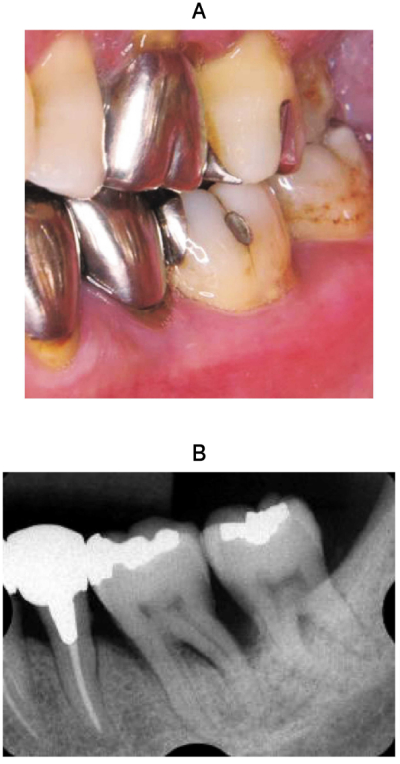

52歳の女性。下顎左側臼歯部の違和感を主訴として来院した。慢性歯周炎の診断のもと歯周基本治療を行った。初診時の口腔内写真とエックス線写真を示す。再評価時の歯周組織検査結果の一部を表に示す。

次に下顎左側第一大臼歯に行う処置として適切なのはどれか。1つ選べ。